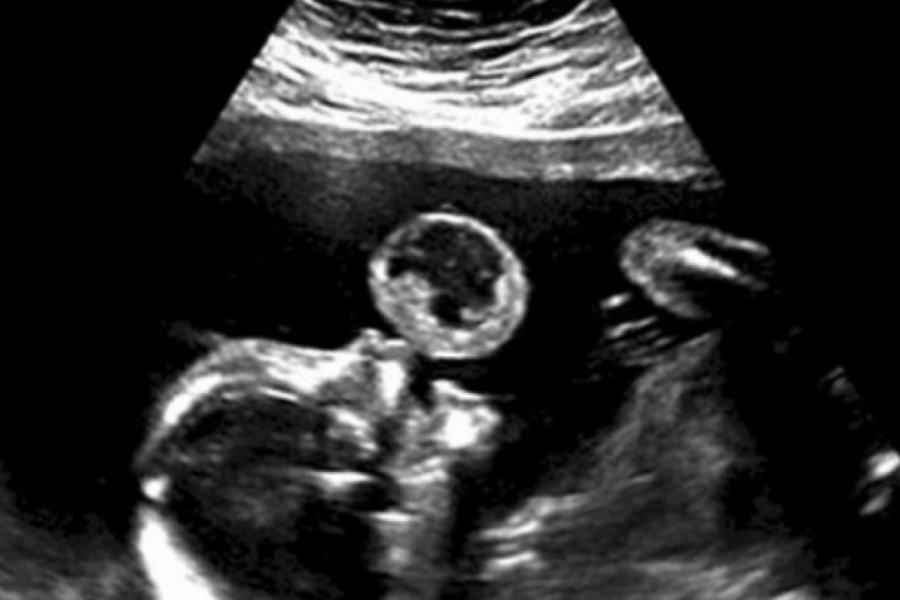

Deca MISLILI SU DA NA ULTRAZVUKU VIDE BEBU KAKO DUVA BALON: Kada je stigla dijagnoza sledili su se - odmah su predložili abortus, ali majka nije htela ni da čuje! (VIDEO) 19:35